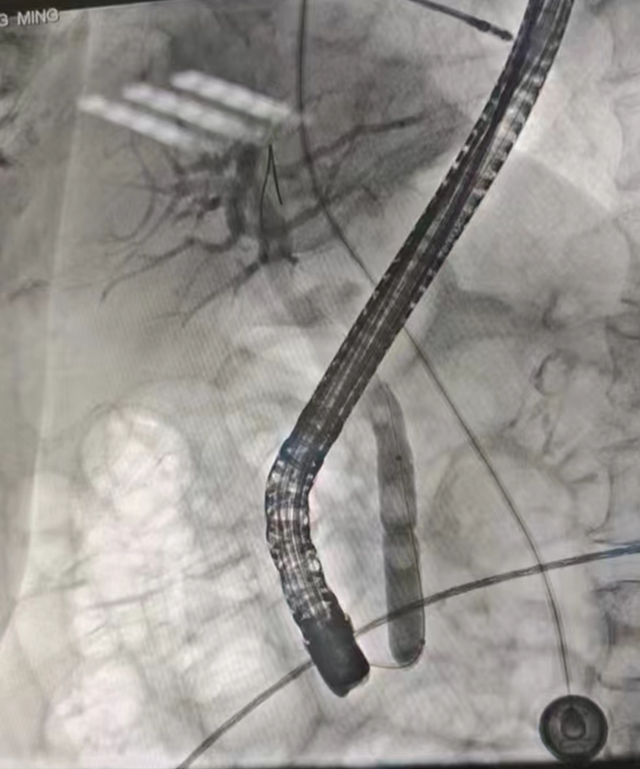

取石网篮取出结石

一切准备就绪后,肝胆胰外科李春桃主治医师、徐云柯医师为张大爷实施了“内镜逆行胰胆管造影(ERCP)+十二指肠乳头球囊扩张(EPBD)+胆道取石+鼻胆管引流术”,术后造影见胆总管通畅,结石取尽,术后第二天张大爷即可进食流质食物,术后五天出院。